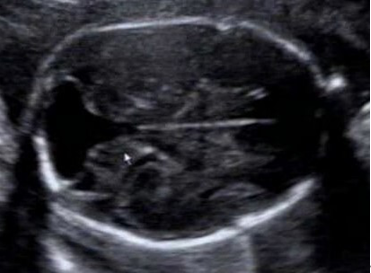

图 1 双侧小脑分离、蚓部缺如,后颅窝池增大与第四脑室相通

胎儿透明隔腔显示不清,小脑下蚓部未显示,第四脑室与后颅窝池相通;室间隔上部回声连续性中断,径约 0.24cm , CDFI 可见过隔血流,主动脉内径约 0.52 ㎝,前壁与室间隔连续中断并骑跨于室间隔之上,骑跨率约 50% ,肺动脉起源于右室,主干内径约 0.49㎝ ,心底大动脉交叉可见(图 1-3 )。